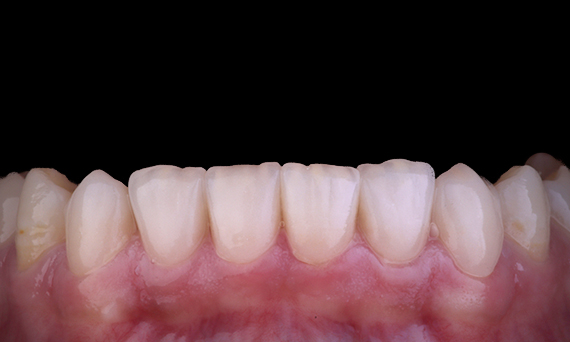

Bij het overwegen van de vervanging van een centrale bovensnijtand door een implantaatgedragen vaste gebitsprothese, zijn casusselectie, planning en zorgvuldige toepassing van behandelmethoden de sleutels tot succes. Onmiddellijke implantaatplaatsing en onmiddellijke restauratie kunnen weefselverlies tot een minimum beperken en resulteren in een zeer esthetisch resultaat. Implantaatplaatsing met een volledig begeleide benadering kan de plaatsingsnauwkeurigheid verbeteren, en de plaatsing van het uiteindelijke abutment of de definitieve restauratie op het moment van plaatsing van het implantaat kan de weefselstabiliteit bevorderen.

Dr. Alan Yap, prosthodontist, Sydney, Australië